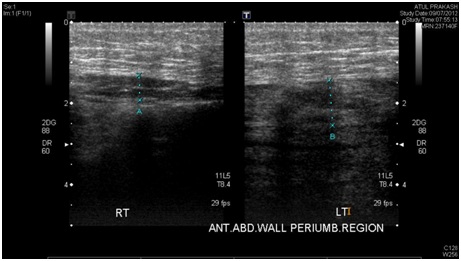

Idiopathic Right Diaphragm Paralysis

Yash H Dubal , et al

Annals of Case Reports